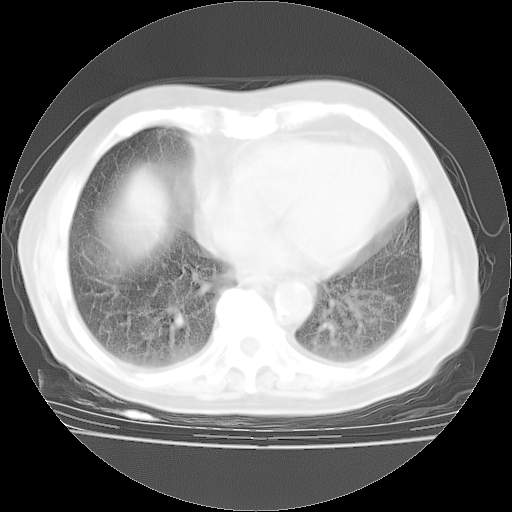

4月28日肺部CT——再次出现类似去年5月9日——磨玻璃样、间有“粟粒样”改变。

4月28日肺部CT

个人阅读4.14日肺部CT平扫:纵隔窗无异常,但肺窗示:双下肺内、后基底段有片絮状侵润影,部位以后基底段为著,以间质改变为主,呈急性肺泡炎征像,和首次住院影像学有相似之处。仅是个人读片,明日请相关专家再读片哈。其它建议同上。